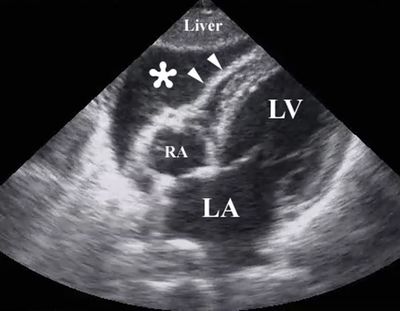

A 20-yo woman after MVA blunt chest injury with pneumothorax, and right rib fractures. After a placement of Rt chest tube, her heart rate of 140 bpm, blood pressure of 80/40 mmHg, 20 mm pulsus paradoxus, distended neck veins, muffled heart sounds, and decreased voltage on ECG. Which of the following findings on Echo would support the diagnosis of cardiac tamponade?

Answer

• Left ventricular collapse

• Right ventricular distention

• Inferior vena cava collapse with increased inspiratory variation

• Early right ventricular diastolic collapse